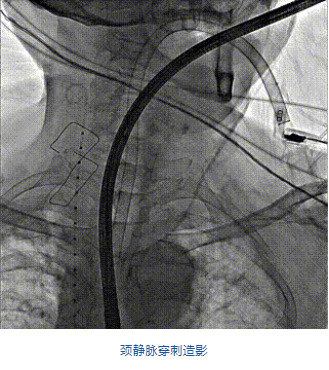

團(tuán)隊前期經(jīng)過多次討論,制定了周密的手術(shù)策略和預(yù)案。由于患者已是近九旬的超高齡老人,傳統(tǒng)外科開胸手術(shù)風(fēng)險極高,純介入經(jīng)血管三尖瓣替換能夠明顯減少創(chuàng)傷。術(shù)中陳茂及馮沅教授結(jié)合體表定位在造影指示下精準(zhǔn)穿刺右側(cè)頸靜脈并預(yù)置兩把血管縫合器。成功建立經(jīng)皮血管入路后在食道超聲和DSA的引導(dǎo)下順利完成人工瓣膜植入,術(shù)后超聲和造影顯示人工三尖瓣同軸性良好,瓣架固定牢靠,無反流和瓣周漏,平均跨瓣壓差降為1mmHg。術(shù)畢收緊預(yù)置的血管縫合器縫線完成止血,縫合效果滿意,在手術(shù)室即刻拔除氣管插管。